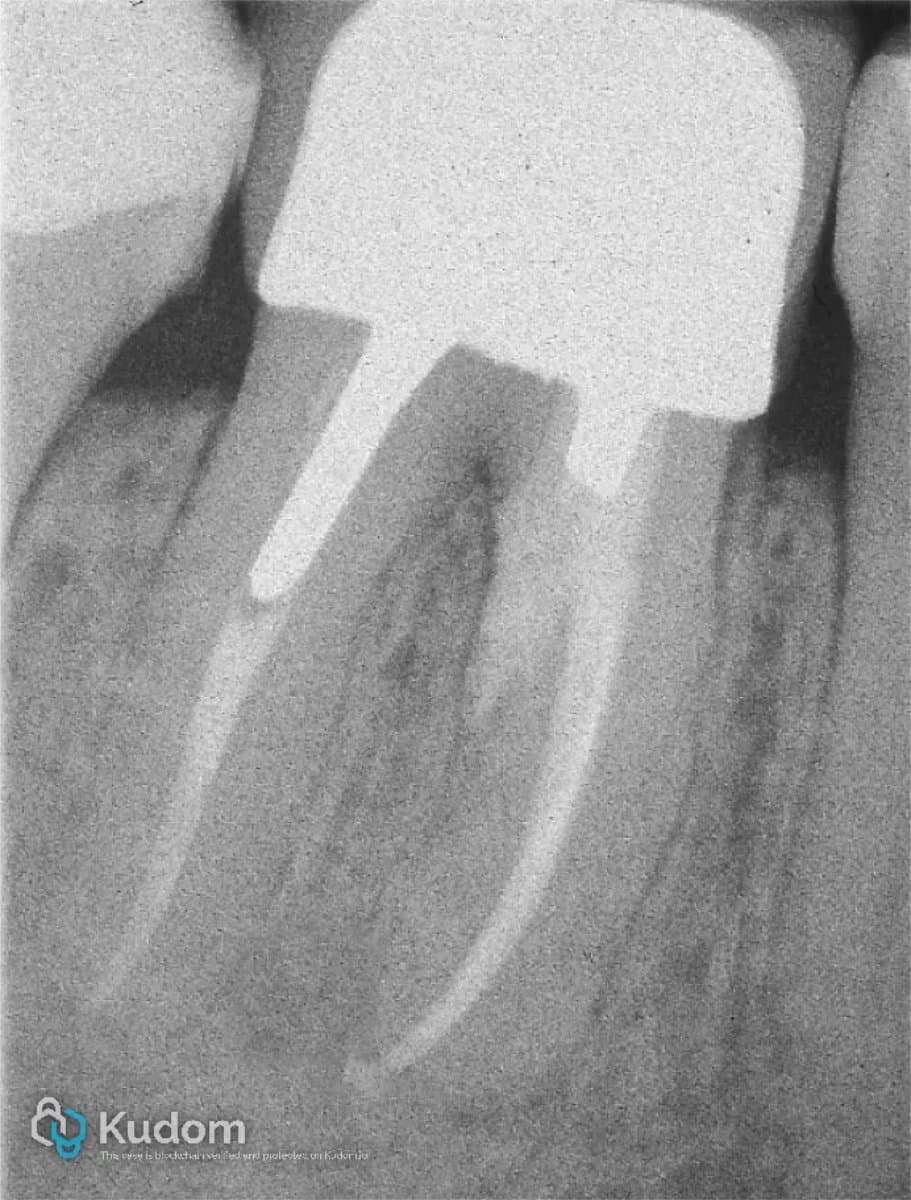

Real clinical cases

Analysis and discussions on endodontic cases, with images and clinical reasoning